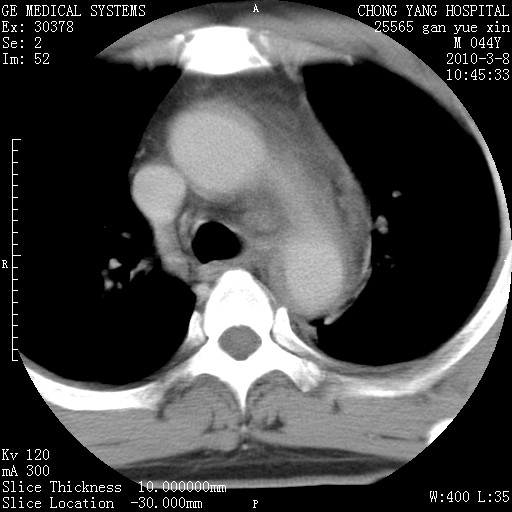

标题: CT24940:主动脉增强,典型病例。 [打印本页]

标题: CT24940:主动脉增强,典型病例。

夹层动脉瘤。

动脉夹层

夹层动脉瘤,典型

主动脉夹层。

动脉夹层的分型:

⒈debakey分型:根据主动脉夹层累及部位,分为三型:ⅰ型:原发破口位于升主动脉或主动脉弓部,夹层累及升主动脉、主动脉弓部、胸主动脉、腹主动脉大部或全部,少数可累及髂动脉。ⅱ型:原发破口位于升主动脉,夹层累及升主动脉,少数可累及部分主动脉弓。ⅲ型:原发破口位于左锁骨下动脉开口远端,根据夹层累及范围又分为ⅲa,ⅲb。ⅲa型:夹层累及胸主动脉。ⅲb型:夹层累及升主动脉、腹主动脉大部或全部。少数可累及髂动脉。

⒉stanford分型:a型:夹层累及升主动脉,无论远端范围如何。b型:夹层累及左锁骨下动脉开口以远的降主动脉。

夹层动脉瘤,少量胸水

夹层动脉瘤;左侧少量胸腔积液。

典型主动脉夹层。